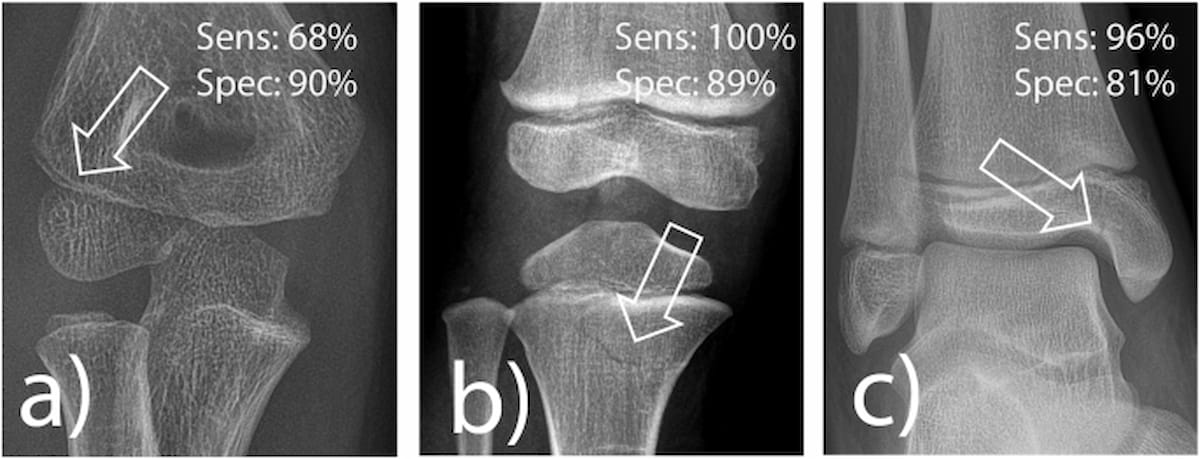

Here one can see examples of radial condyle fracture (A), proximal tibia fracture (B) and medial malleolus fracture (C) that are frequently misdiagnosed. Artificial intelligence (AI) software offered 100 percent sensitivity for proximal tibia fractures, 96 percent sensitivity for medial malleolar fractures and 68 percent sensitivity for radial condyle fractures, according to a newly published study. (Images courtesy of European Radiology.)

The study authors also assessed the AI software for the detection of proximal tibia fractures, medial malleolus fractures and radial condyle fractures, all of which are commonly missed in practice and have significant medicolegal considerations, according to the study authors.

For proximal tibia fractures, the AI software provided 100 percent sensitivity and 89 percent specificity. The study findings also revealed that medial malleolar fractures on X-ray were detect by the AI software with 96 percent sensitivity and an 81 percent specificity.

While the AI software did offer a 90 percent specificity for radial condyle fractures, the study authors acknowledged a lower sensitivity of 68 percent.